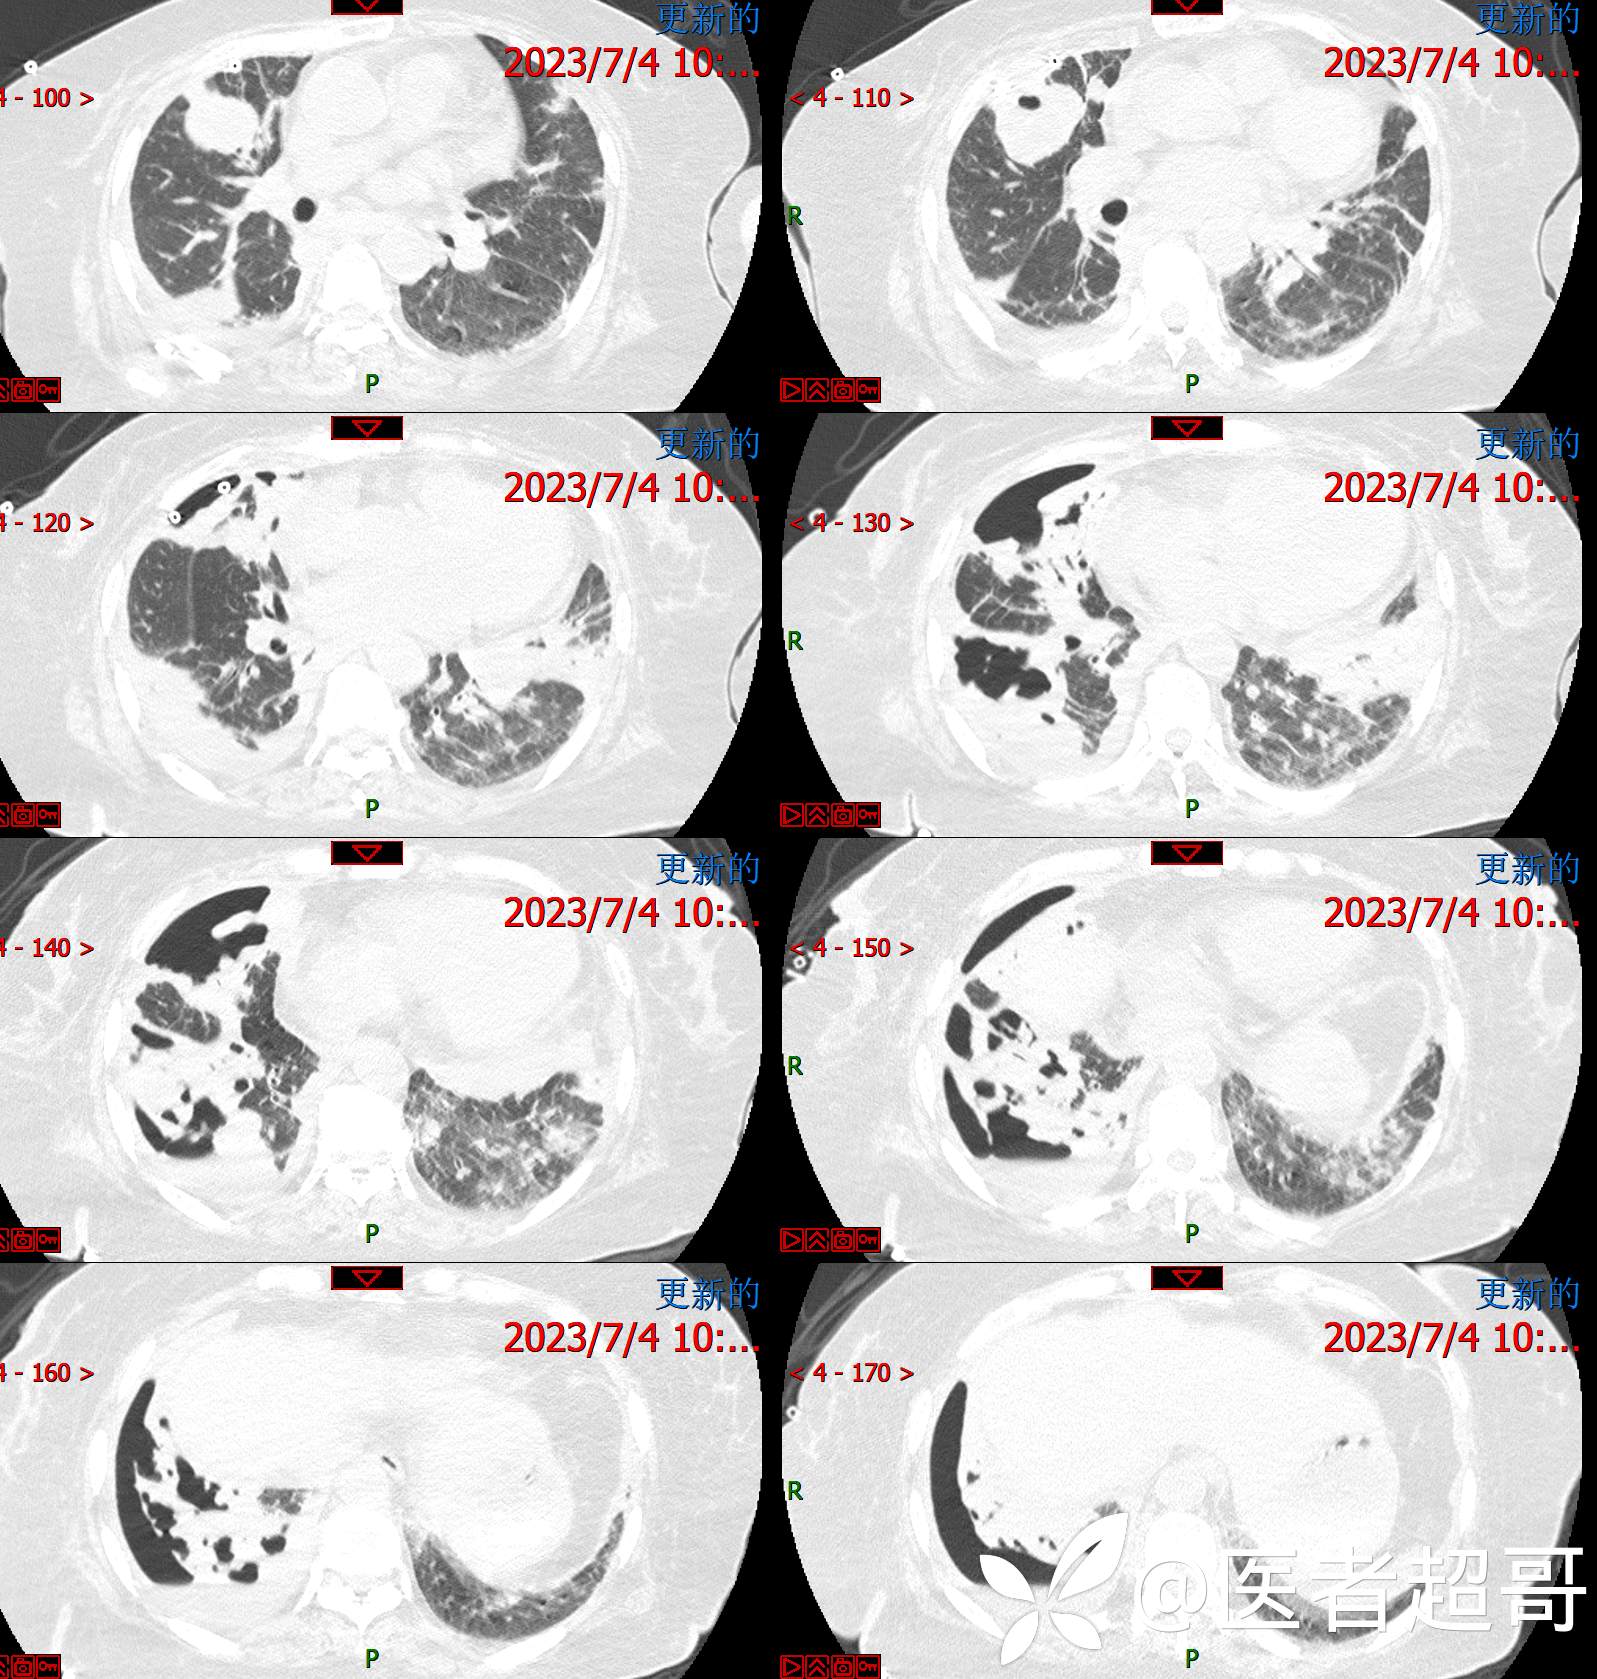

现病史:患者于4年前在神经内科住院期间监测血糖高,随机血糖29.4mmol/l,经治疗好转出院,出院诊断“锥体外系反应 2型糖尿病 感冒”,院外自行口服“二甲双胍 2片 bid,格列吡嗪胶囊 1粒 bid”降糖治疗,平素未规律监测血糖。约3年前感四肢麻木不适,无明显疼痛,无肢体活动障碍,未特殊治疗。7天前出现乏力、憋气不适,伴有流清涕,无发热、寒战,咳嗽不著,有痰不易咳出,食欲减退,无腹痛、腹泻,无恶心、呕吐,患者发病后于当地诊所就诊,监测血糖偏高(具体数值不详),给予输液治疗(具体药物不详),效果欠佳,2天前感乏力、憋气加重,今急来诊,急诊完善胸部CT平扫示:双肺多发肿瘤表现,纵膈淋巴结肿大,心包少量积液,建议三周后复查除外隐匿性骨折;血糖32mmol/l,为求进一步诊疗,门诊以“糖尿病”收入我院。

2023.07.04检查: